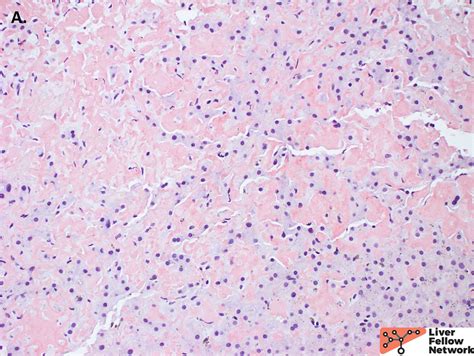

The Congo Red Stain works by binding to the beta-pleated sheet structure of amyloid fibrils. When Congo Red dye is applied to a tissue section, it interacts with the amyloid deposits, resulting in a red color under normal light. However, when viewed under polarized light, the stained amyloid deposits exhibit a distinctive apple-green birefringence. This unique optical property is crucial for the accurate identification of amyloid proteins.

Interpreting the results of the Congo Red Stain involves examining the tissue sections under both normal and polarized light. Under normal light, amyloid deposits appear red. However, the true diagnostic value of the stain is revealed under polarized light, where the amyloid deposits exhibit a characteristic apple-green birefringence. This birefringence is a result of the interaction between the Congo Red dye and the beta-pleated sheet structure of the amyloid fibrils.